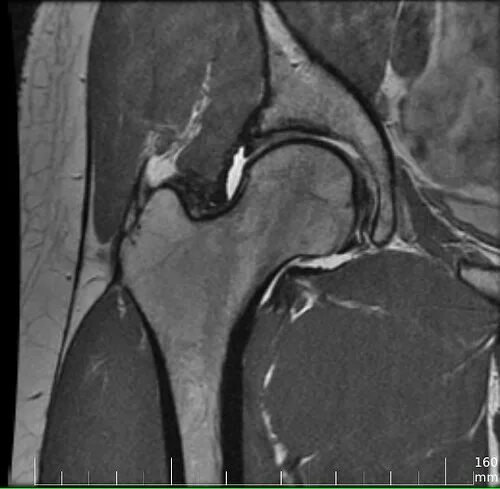

Мрт тазобедренного сустава в минске